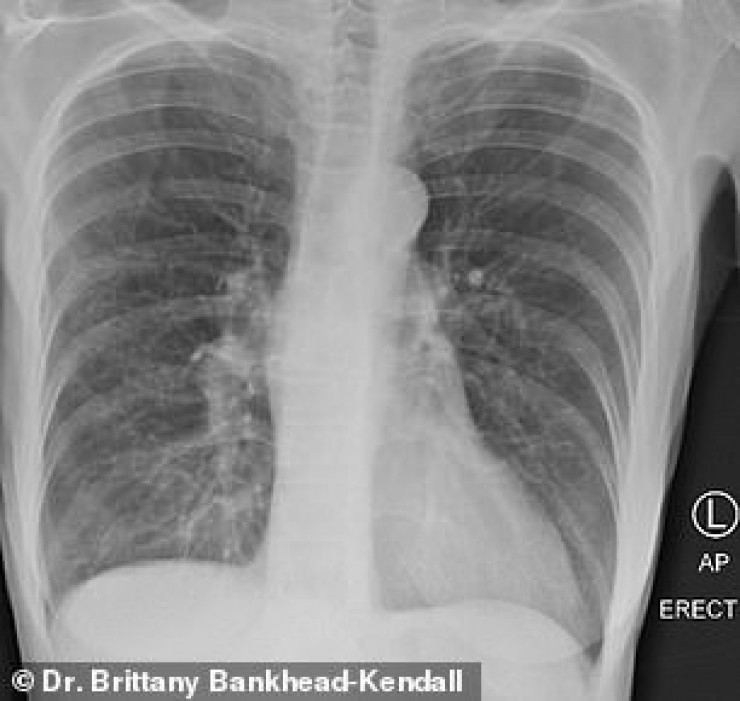

Доцент Центра медицинских наук Техасского технологического университета, доктор Бриттани Бэнкхед-Кендалл показала три рентгеновских снимка легких: здорового человека, курильщика и пациента с коронавирусом.

По словам хирурга, легкие выздоровевших пациентов с COVID-19 выглядят намного хуже, чем у курильщиков. Снимок выглядел почти полностью белым. Врач пояснила, что помутнение легких обычно указывает на то, что они наполнены такими веществами, как жидкость или бактерии, а также плотными рубцами и повреждениями.

У курильщика они частично побелели от рубцов, и снимок выглядит слегка туманным.